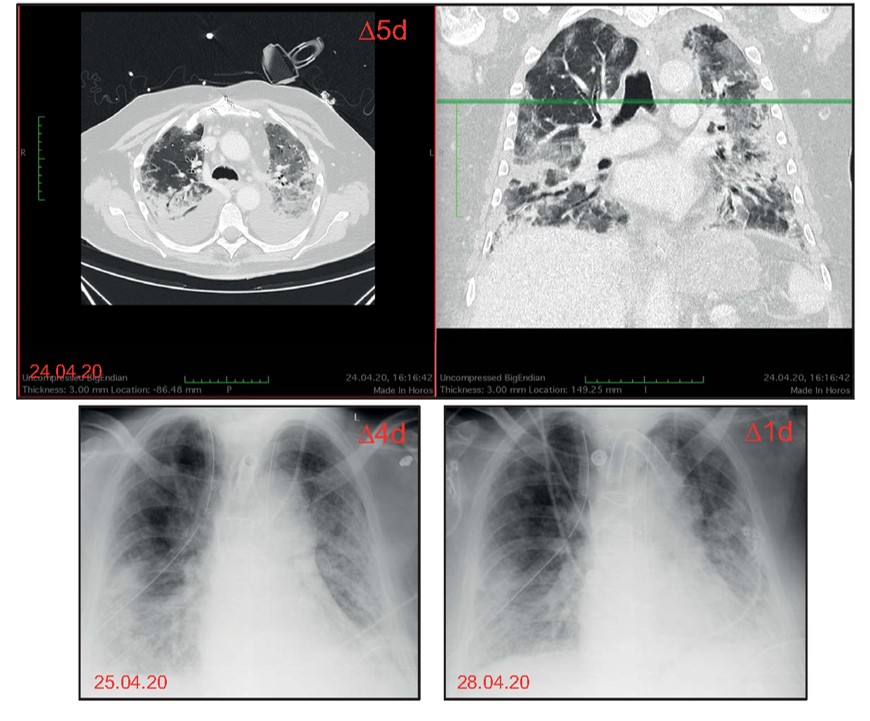

HeiCuDent Kasuistik Nr. 9: Obduktion eines 70-jährigen Patienten mit COVID-Infektion

Bildgebung

Klinischer Verlauf

- Initiale Behandlung auf der Normalstation

- Verlegung auf Intensivstation und Intubation bei zunehmender respiratorischer Verschlechterung

- Anlage einer extrakorporalen Membranoxygenierung (ECMO)

- Patient verstirbt im Verlauf trotz maximaler Therapieeskalation

- Obduktion im pathologischen Institut

- Lungen schwer und konsistenzvermehrt

Makroskopischer Aspekt der lamellierten Lungen.